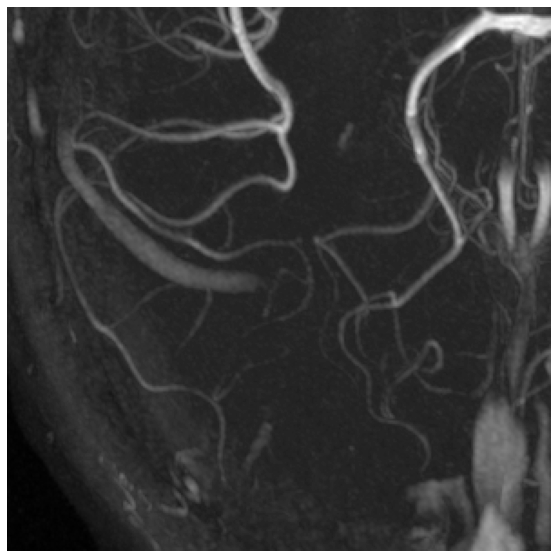

We tested our approach on three data sets. The Brain comprises 14 light microscopy scans of mouse brain, sized . We use 10 of them for training and 4 as a validation test. Neurons contains 13 light microscopy scans of mouse neurons, sized . We use 10 for training and 3 for validation. MRA is a publicly available set of Magnetic Resonance Angiography brain scans [3]. We crop them to size by removing their empty margins, and use 31 annotated scans for training and 11 for validation. A sample image from each data set can be found in Fig. 4.

| Brain | Neurons | Neurons | MRA | |

|---|---|---|---|---|

| Input | ![]() |

![]() |